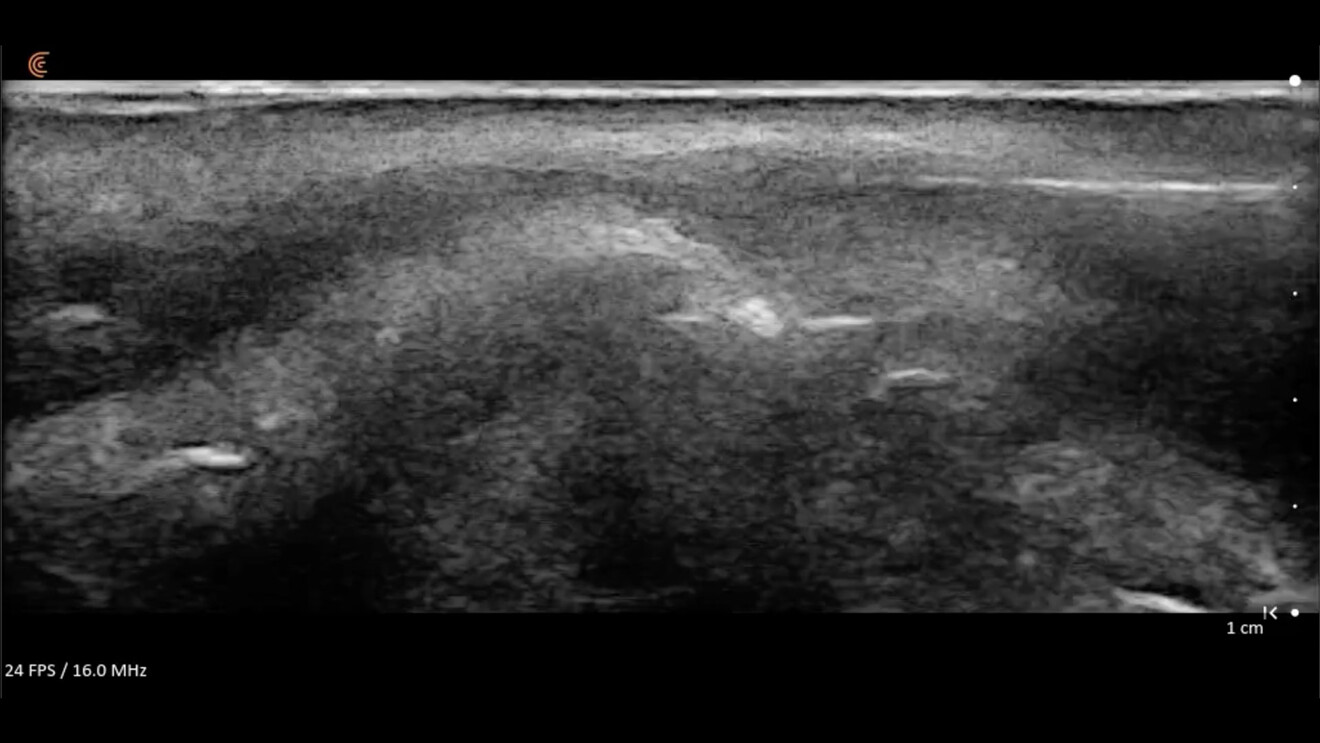

• Mappatura vascolare dinamica: l’integrazione di B Mode, Color Doppler e del Power Doppler rappresentano la frontiera della sicurezza. Vasi critici posti in posizioni anatomiche critiche come l’arteria angolare possono avere decorsi variabili. L’esame ecografico permette di mappare questi vasi prima di inserire l’ago, scegliendo il piano di correzione (superficiale o profondo) che garantisca l’assenza totale di rischio vascolare occlusivo intravascolare o compressivo extravascolare (Fig. 9).

Fig. 9 - L’arteria angolare in Color Doppler.